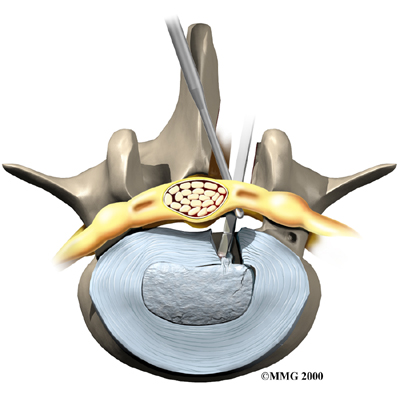

Microdiscectomy

Microdiscectomy is becoming the standard surgery for lumbar disc herniation. The procedure is used when a herniated disc is putting pressure on a nerve root. It involves carefully taking out part of the problem disc (discectomy). By performing the operation with a surgical microscope, the surgeon only needs to make a very small incision in the low back. Categorized as minimally invasive surgery, this surgery is thought to be less taxing on patients. Advocates also believe that this type of surgery is easier to perform, that it prevents scarring around the nerves and joints, and that it helps patients recover more quickly.

Related Document: FYZICAL South Hagerstown's Guide to Lumbar Discectomy